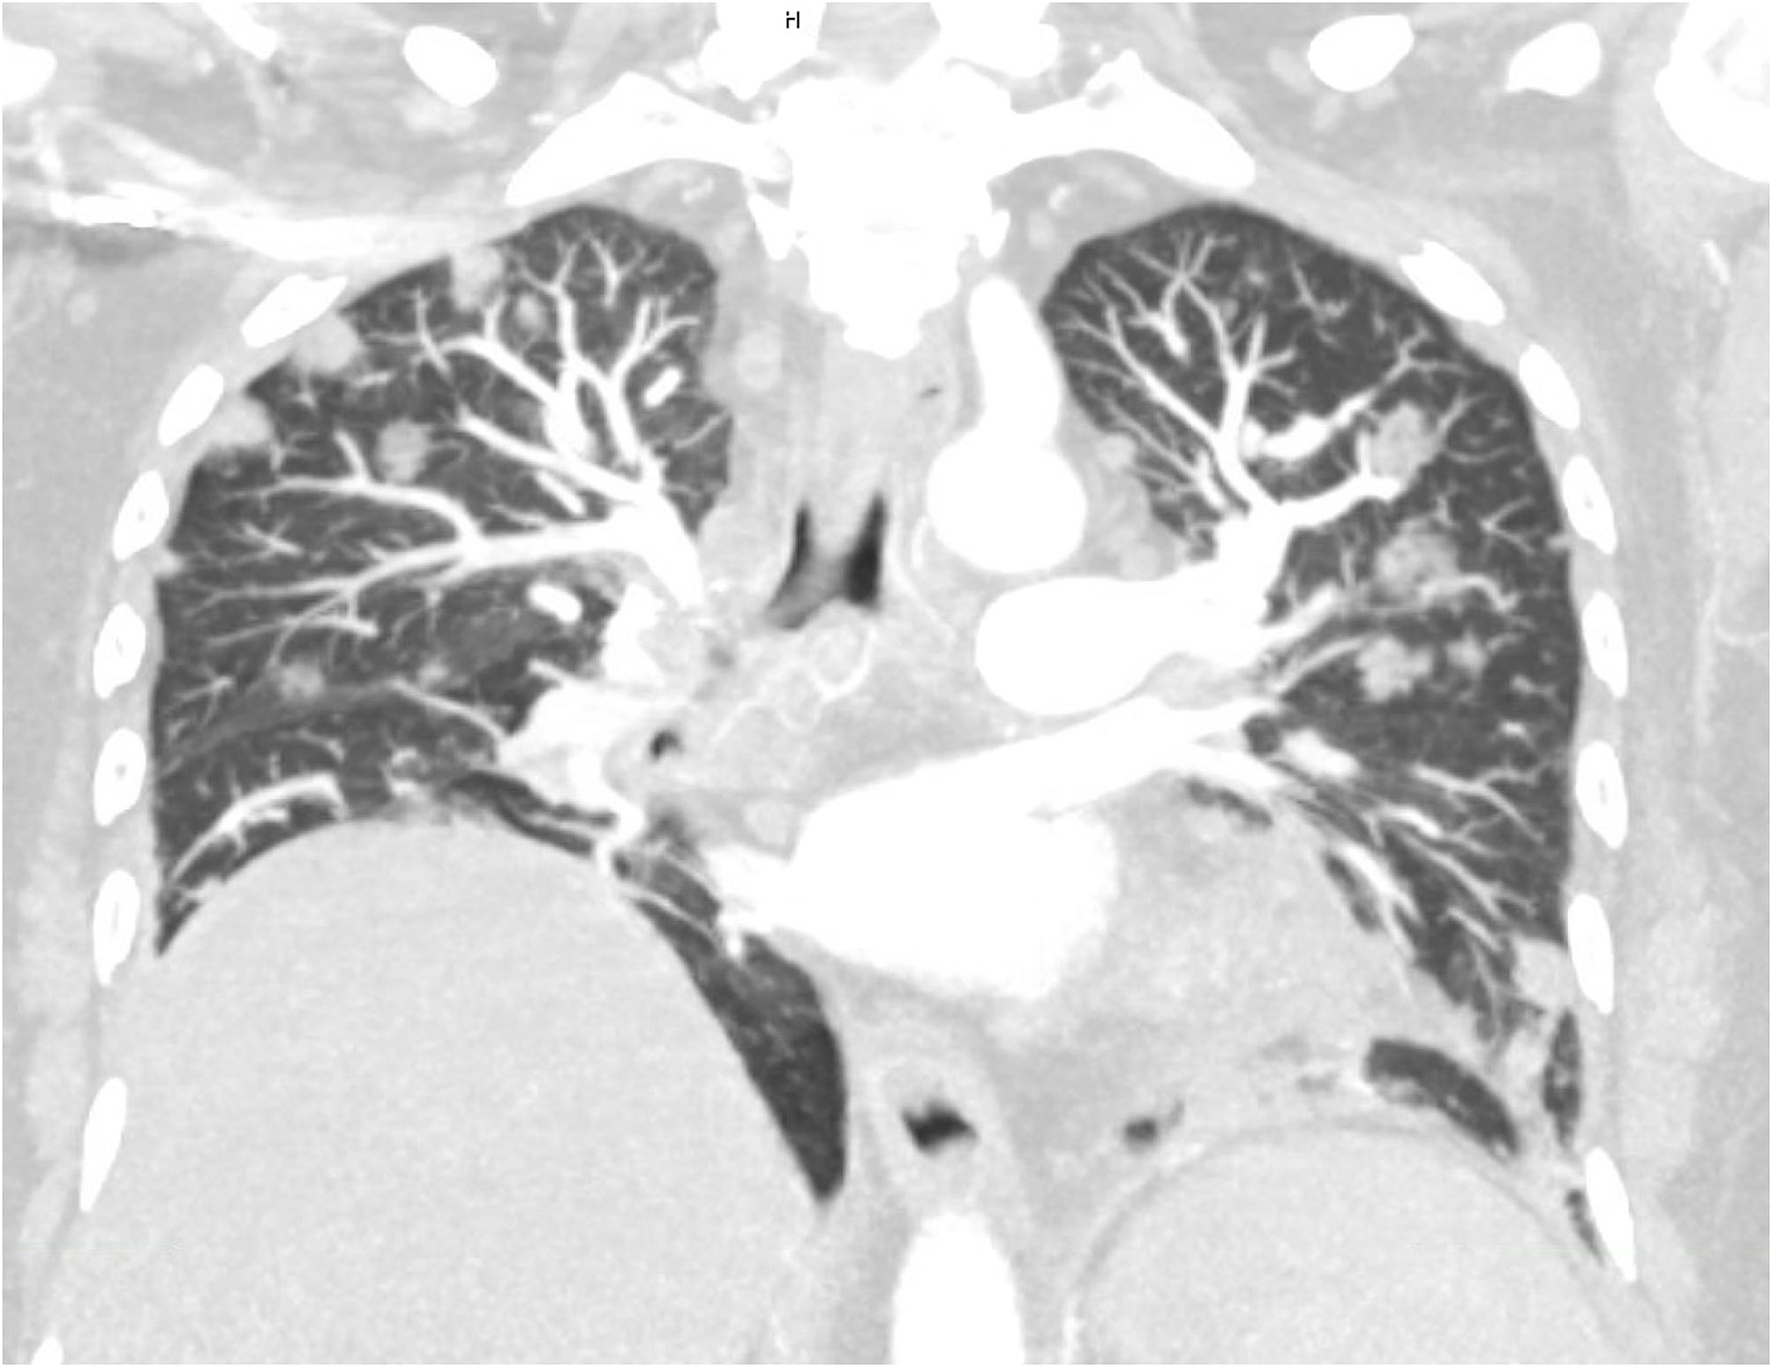

FIGURE 1

www.frontiersin.org

Figure 1. Maximal intensity projection (MIP) of multi-planar reconstruction computed tomographic angiography at admission day. Multiple septic embolic lesions appearing as nodules are present predominantly in the subpleural as well as peribronchovascular area, while close topographic proximity to the branching pulmonary arteries is noted.

A 63-year-old Caucasian female was admitted to the intermediate care unit with a first diagnosis of diabetes mellitus and an infection-associated metabolic (keto)-acidosis (pH 7.16). Initially, the patient was hypovolemic, disoriented, tachypneic, hypoxemic, complained about epigastric pains, and loss of vision on the left eye. The serum glucose and the inflammation markers were markedly elevated (Table 1). The initial management included fluid resuscitation, insulin therapy and an empiric antibiotic treatment with piperacillin/tazobactam after blood- and urine-culture sampling. Due to persisting hypoxemia high-flow oxygen supplementation therapy was necessary and a CT was performed. This revealed signs of pyelonephritis, a renal vein thrombosis and bilateral subsegmental lung emboli co-localizing with multiple round and wedge-shaped infiltrates and a large consolidation in the right lower lobe (Figures 1, 2).